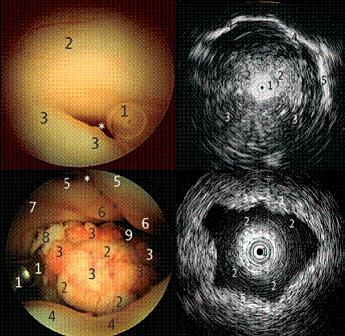

Example of ultrasound used in neurosurgery

Examples of use of the ultrasound probe in neurosurgery

A (top left), aqueduct. The sonoprobe (1) is entering the aqueduct (white asterisk) at the posterior third ventricle formed by hypothalamus (2) and posterior commissure (3).

B (top right), aqueduct and posterior fossa. The sonoprobe (1) is inside the aqueduct of the mesencephalon (2). As the zoom is very low, the posterior fossa is scanned with the cerebellum (3), clivus, and petroclival border (4), as well as the tentorial notch on the right side (5).

C (bottom left), fourth ventricle. The sonoprobe (1), as well as the inferior vermis (2) bulging into the ventricle covered by the variant of a circular plexus (3). The superior medullary velum (4) limits the inferior view while a view into the depth of the foramen of Magendi (9) is possible. The facial colliculus (6) and medial eminence (5) are seen on both sides, divided by the medial sulcus (asterisks). Laterally, the vestibular area (7) is visible, as is the entry to the foramen of Luschka (8).

D (bottom right), fourth ventricle scan. The sonoprobe (1) is in the fourth ventricle looking into the parenchyma of facial colliculus (3), superior cerebellar peduncle (4), and superior medullary velum and superior vermis (5).